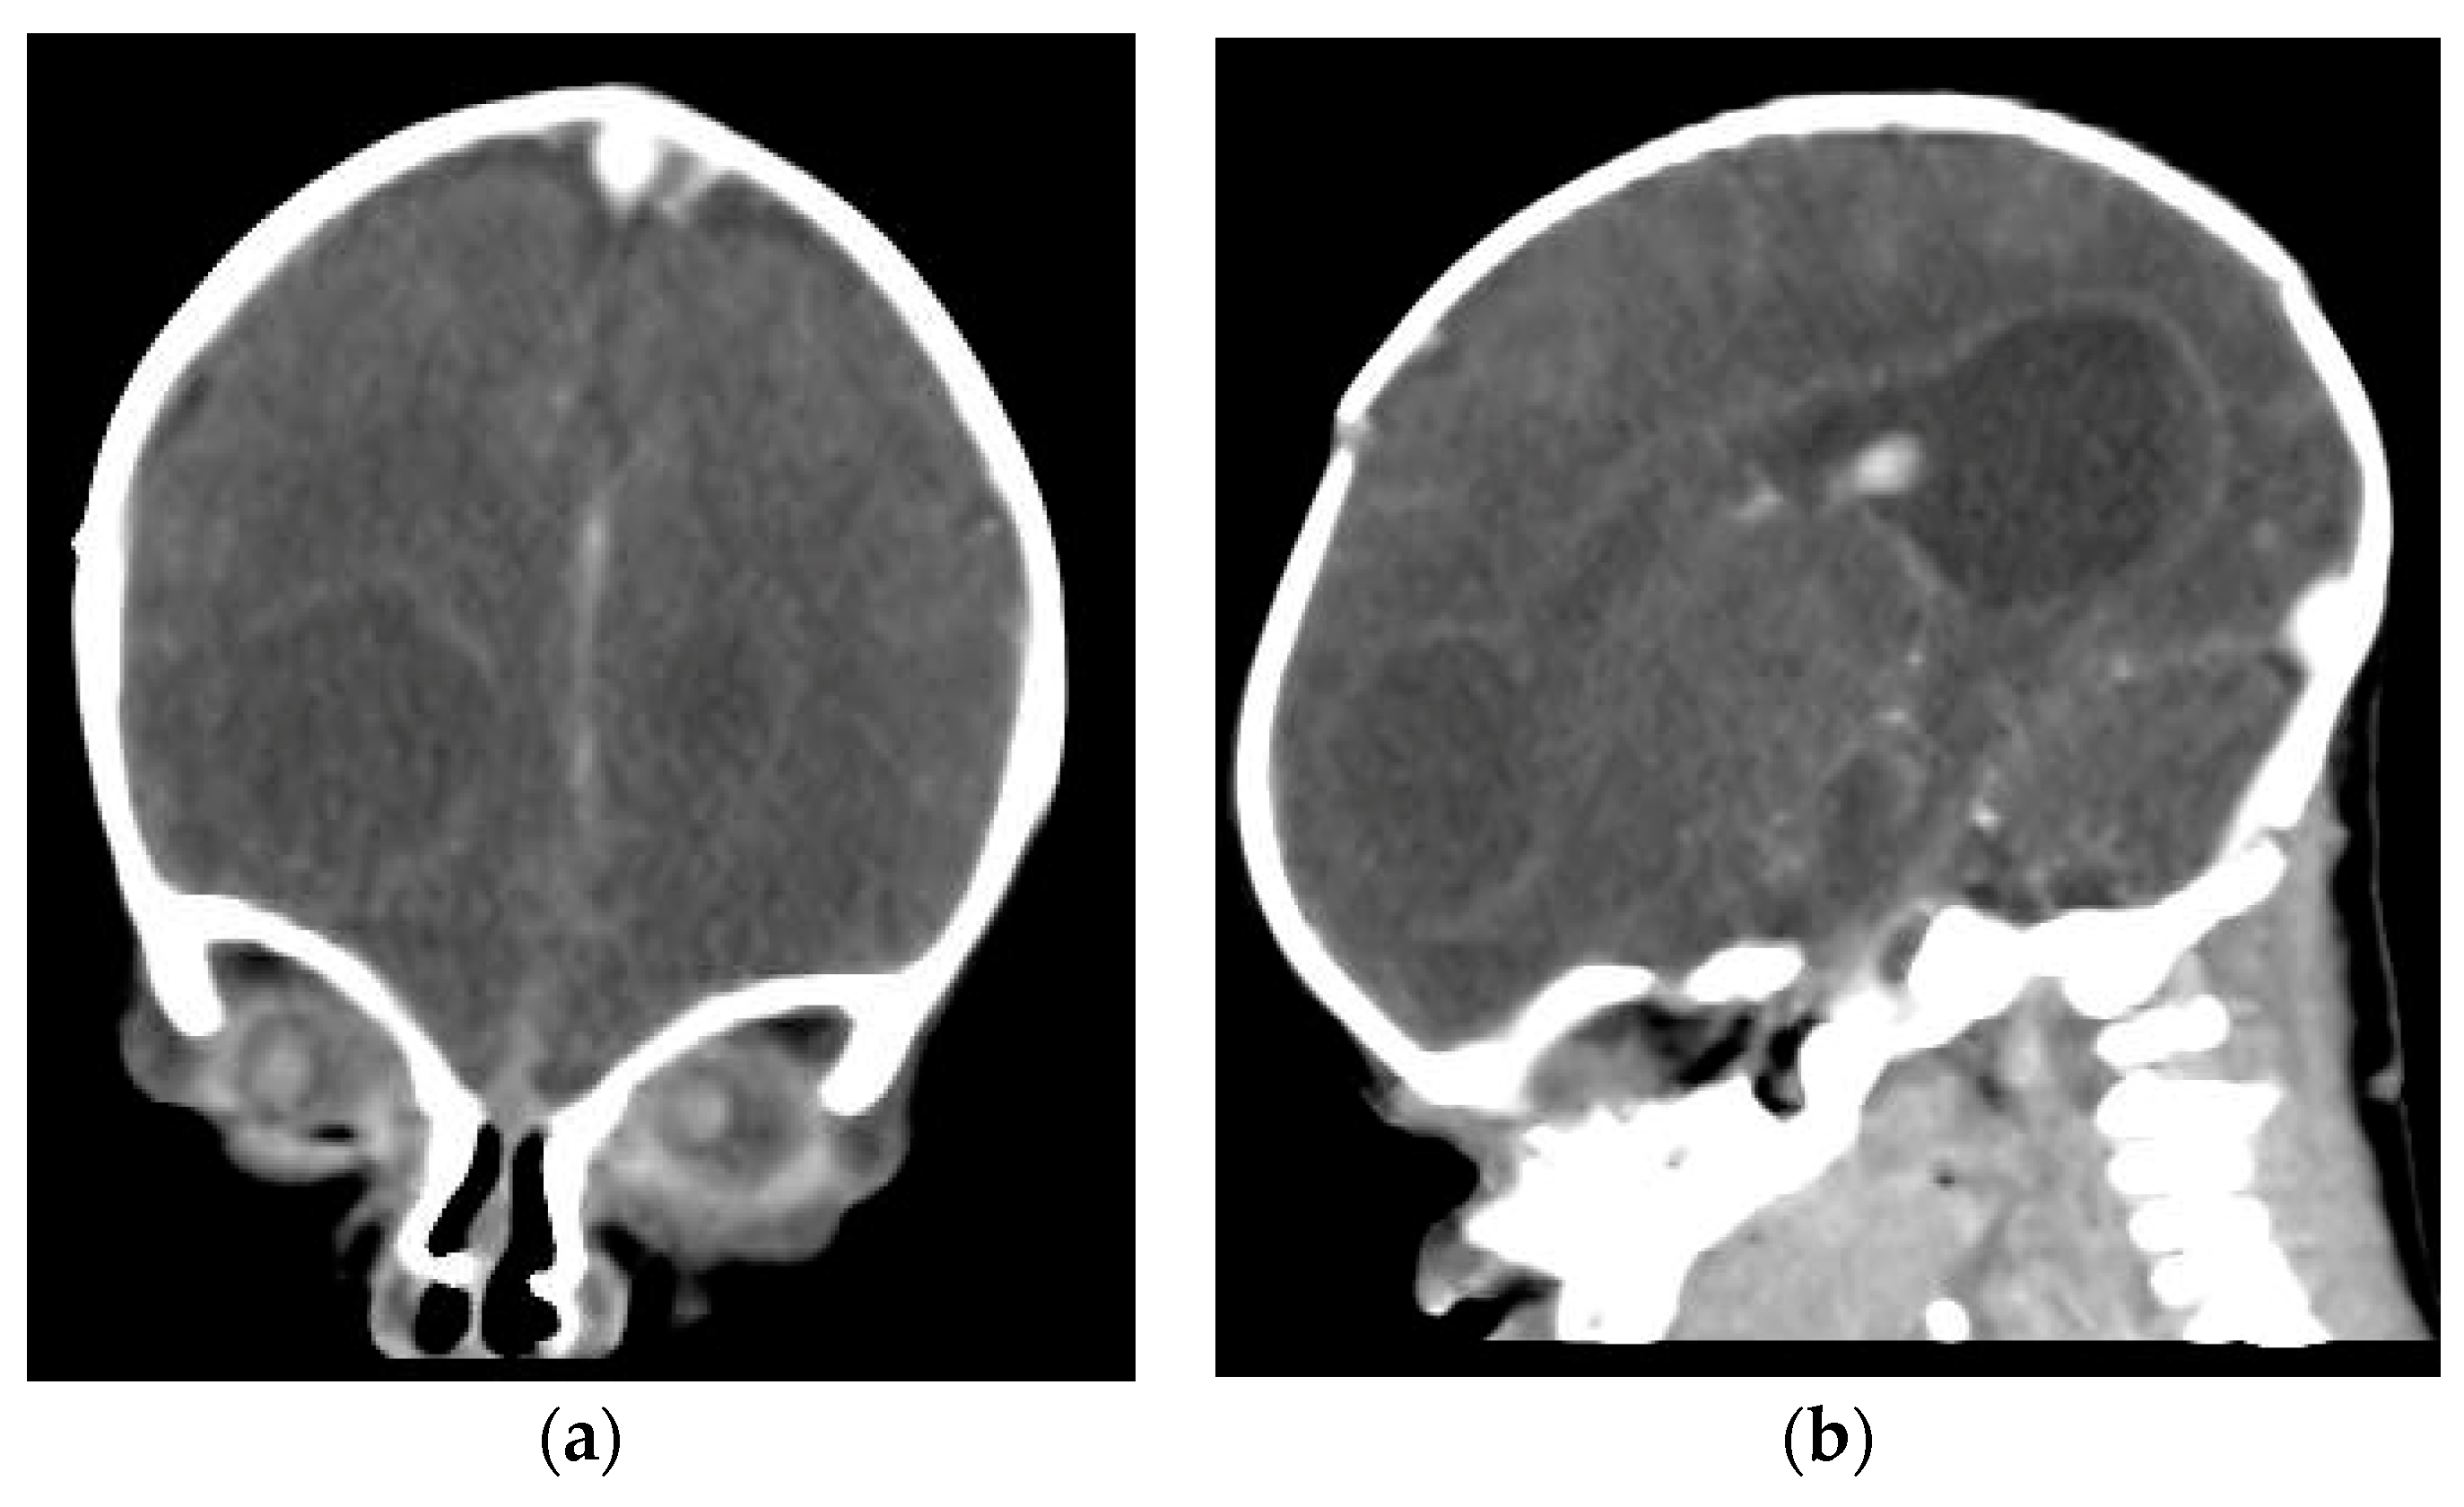

2. Case Presentation